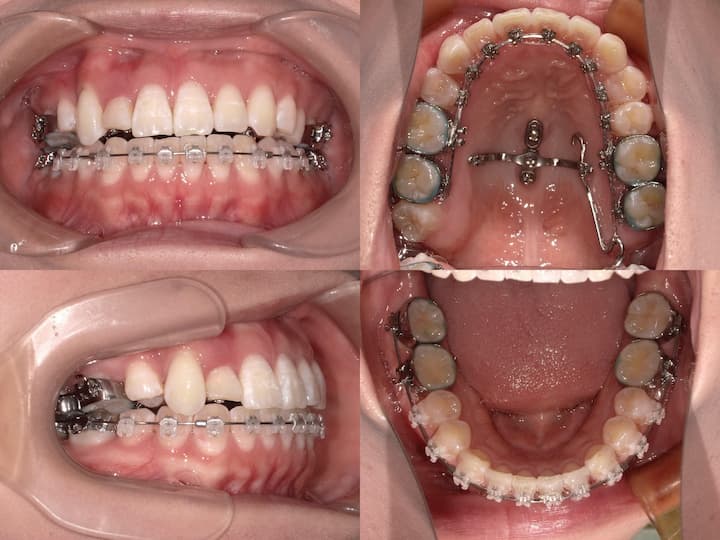

矯正装置

ハーフリンガル矯正装置を採用し、上顎は舌側矯正装置(リンガルブラケット)、下顎は唇側矯正装置(ラビアルブラケット)を使用しました。上顎大臼歯の圧下とアンカレッジコントロール

本症例の治療成功の鍵は、上顎大臼歯の確実な圧下とAngleⅠ級臼歯関係の維持にあります。以下の治療メカニクスを採用しました。

・i-station(歯科矯正用アンカースクリュー)の植立:正中口蓋縫合部に植立し、上顎大臼歯の固定源として使用

・上顎大臼歯の圧下:i-stationからの圧下力により、上顎大臼歯を垂直的に圧下

・上顎大臼歯の固定:抜歯スペース閉鎖時の近心移動を防止し、AngleⅠ級臼歯関係を維持

咬合平面のコントロール

上顎大臼歯の圧下に際し、適切な咬合平面を維持するため、以下の対策を講じました。・フルサイズワイヤーの使用:.018×.025インチTMA(チタンモリブデン合金)ワイヤーを使用し、臼歯部のみが選択的に圧下するように設計

・パラタルバーの装着:上顎大臼歯の幅径を維持し、歯列弓形態の安定を確保